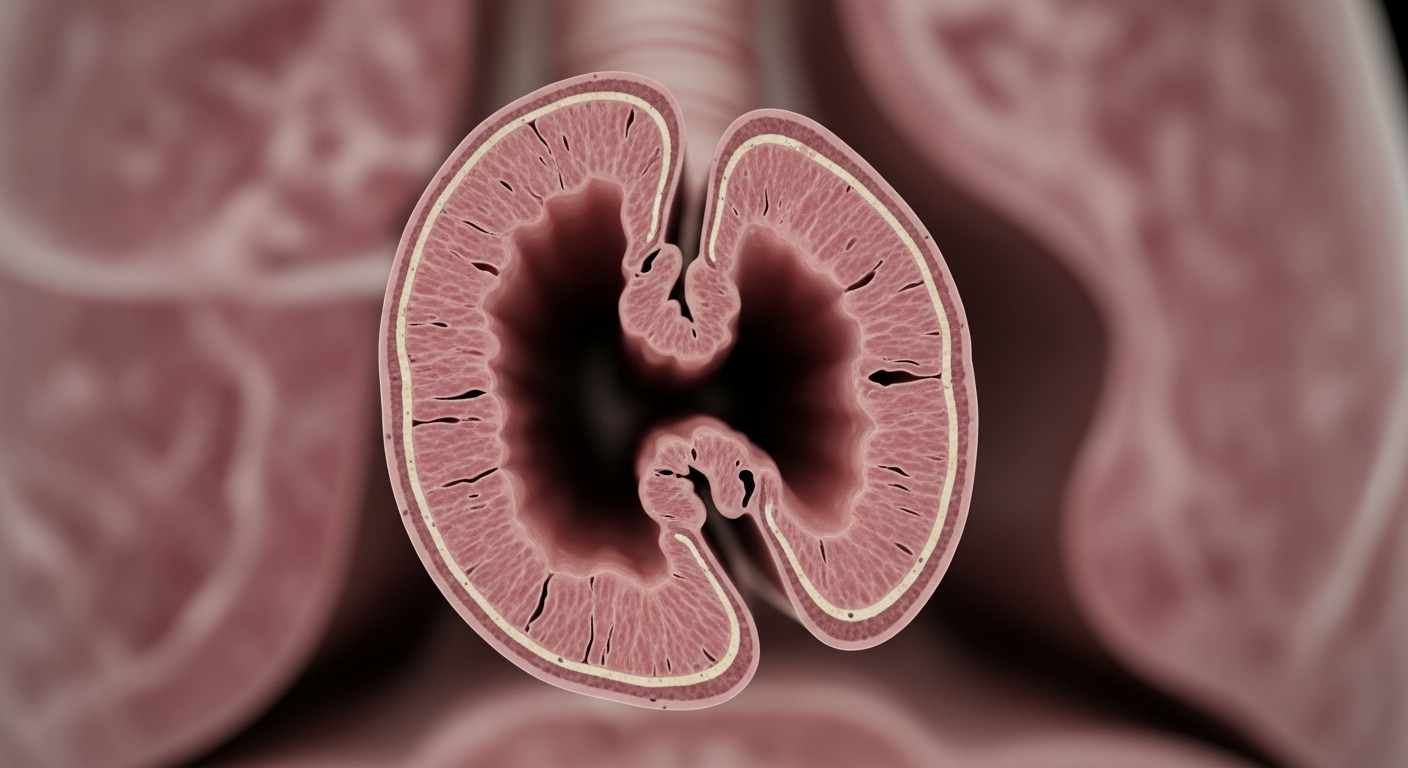

5.2. Tổn thương phổi không hồi phục, mất chức năng phổi

Tình trạng xẹp phổi kéo dài hoặc nhiễm trùng tái phát liên tục sẽ hủy hoại nhu mô phổi vĩnh viễn. Lúc này, dù có thể mở thông phế quản, lá phổi cũng khó có thể phục hồi chức năng ban đầu, thậm chí có thể phải cắt bỏ một phần hoặc toàn bộ.